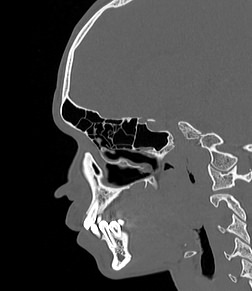

Лицевой череп состоит из крупных костей (верхняя и нижняя челюсти, лобные кости, скуловые кости) и сгруппированных вокруг них остальных мелких костей. При травмах лицевых костей часто наблюдается смещение мелких отломков, которые не видны при обычной рентгенографии. Мультиспиральная компьютерная томография позволяет детально изучить кости лицевого черепа, а также углубления, которые являются вместилищем для важных органов (глазницы, полость носа, ротовая полость).

Метод КТ основан на применении рентгеновского излучения и различной способности тканей поглощать рентгеновские лучи. Костные структуры обладают наибольшей плотностью по сравнению с другими тканями, поэтому в большей степени поглощают рентгеновские лучи и лучше всего визуализируются при данном исследовании.

КТ костей лица является наиболее информативным методом диагностики травм лицевого черепа, посттравматических деформаций, аномалий развития, инородных предметов в носовой полости и околоносовых пазухах. Кроме того, мультиспиральная КТ применяется при воспалительных заболеваниях ЛОР-органов, а также для выявления опухолевых образований доброкачественного и злокачественного характера.

Детальные изображения костей лицевого черепа получаются за счет вращения трубки томографа с излучателями рентгеновских лучей вокруг объекта исследования. В аппаратах увеличено количество сверхчувствительных детекторов, позволяющих производить множество послойных снимков с толщиной среза от 0,5 мм, которые затем преобразуются в трехмерные пространственные модели черепа. Такие инновационные возможности аппаратов обеспечивают проведение точной и достоверной диагностики.